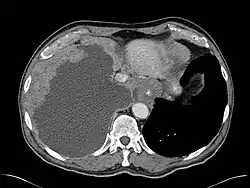

Mesothelioma Overview

Pathology

- Sarcomatous

- Epithelial (best prognosis of 3 subtypes)

- Mixed

- Pleural Involvement